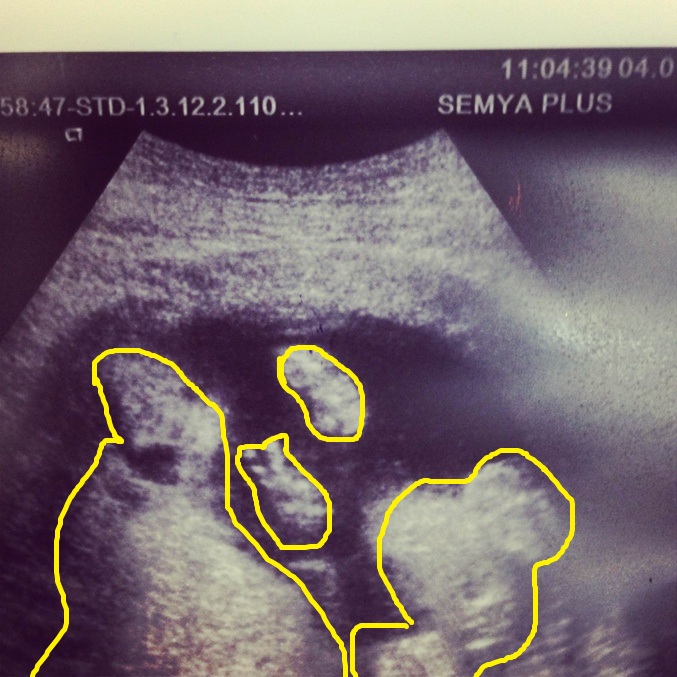

Правой ручкой показывает пис Левой просто ладошка кажется все очевидно)))

Я фотку обвела,но она не грузится, я вообще не могу понять, где что((( (ой,загрузилась, вон, выше)

вы обвели два овальчика, это ручки, на нижней как раз два пальчика торчат

2 обведенных кружка маленьких  левый это правая рука  правый кружок это левая рука)))